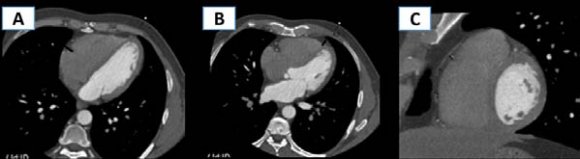

As can be seen from these data, the historical concept of the relationship between obesity and cardiovascular disease (CVD) has changed in recent years, considering the emerging new results from prospective studies. EAT is fatty tissue located between the myocardium and the visceral pericardium, while paracardial fat is located outside the heart. Epicardial and paracardial adipose tissue targets in-depth studies due to their close topographic and anatomical location to the coronary arteries and myocardium (Fig. 1). The study of the relationship between the volume of EAT and the state of the coronary arteries (CA) in patients with coronary artery disease can be essential for predicting the course of CVD. The study of the diversity of pathogenetic mechanisms of increasing the risk of CVD development due to the summation of the effects of a fat depot on CA atherogenesis is a promising area of preventive cardiology. In this regard, the purpose of this study was to assess the amount of EAT using volumetric MSCT and to study the correlation of this indicator with the degree of atherosclerotic lesions of the coronary artery.

The measurement of the EAT thickness was carried out in the projection s/3 RCA, d/3 LAD at the level of the interventricular septum and along the lateral wall of the right ventricle (Fig. 2), taking into account the average value of all measurements.

The area of EAT was calculated at the basal level of the ventricles of the heart along the short axis, as well as the area of adipose tissue of the pericoronary region at the level of the left coronary artery (LCA) trunk, n/3 of the anterior interventricular branch (AIVB) and n/3 of the right coronary artery (RCA) with manual designation of the locus of interest and automatic measurement of the EAT area. The volume of EAT was calculated by MSCT angiography of CA using the "Fat measurement" option. Produced targeted isolation of EAT in the density range of -150-70 HU, followed by manual correction of the epicardial boundaries and automatic determination of adipose tissue volume in a given area with a 3D reconstruction of the total volume. Statistical analysis of the data obtained was carried out using the Stattech software package.

It is clearly demonstrated by MSCT tomograms with 3D reconstruction of the EFT, where its boundaries are traced on axial sections and 3D reconstruction of the CA.